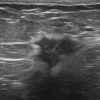

Ung thư vú

» Thông tin: Nữ giới – 56 tuổi.

» Lâm sàng: Khối tuyến vú.